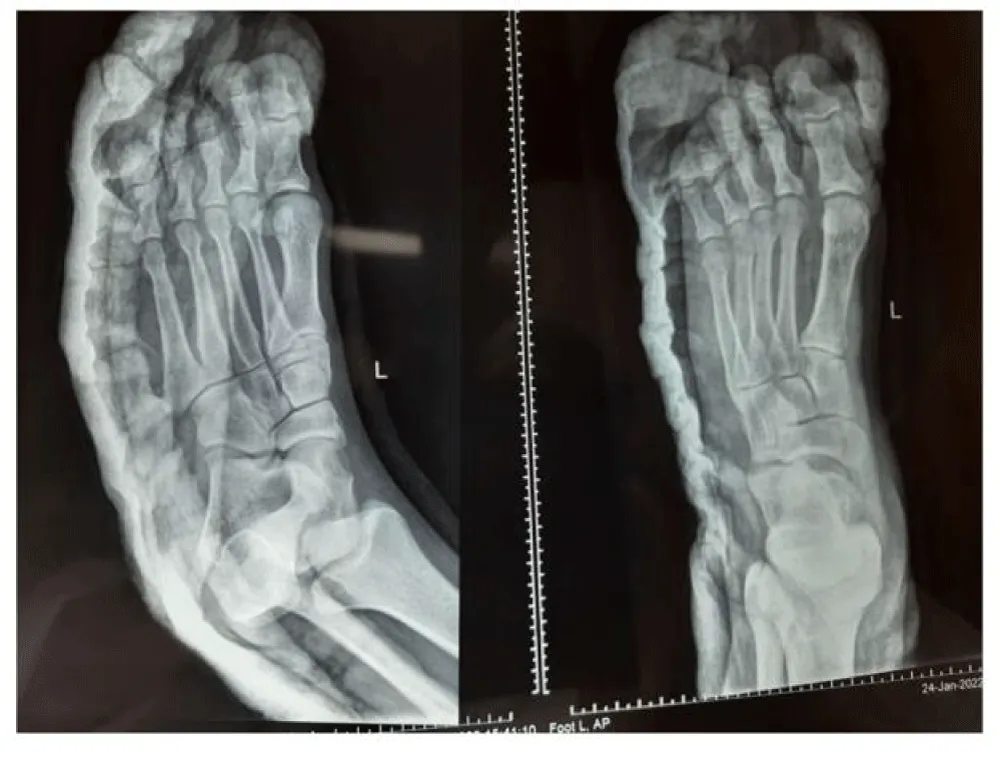

The patient was admitted and, after a preliminary workup, was scheduled for closed / open reduction under anesthesia. He underwent closed manipulation and reduction under General anesthesia by simultaneous reverse mode of injury manipulation of all four toes to free any soft tissue impingement. The joints were stable and congruent after closed reduction without any need for K-wire stabilization (Figure 2). Post buddy toe operatively strapping with below-knee plaster of Paris posterior back slab was applied for immobilization of the foot in neutral position. Patient was kept non-weight bearing for 05 weeks, followed by progressive weight bearing as tolerated.At 12 weeks (Figure 3), follow up patient was doing fine with full weight bearing and had returned to pre-injury level activities with good painless range of toe movements. The patient was followed for a period of 06 months post-injury without any complaints.